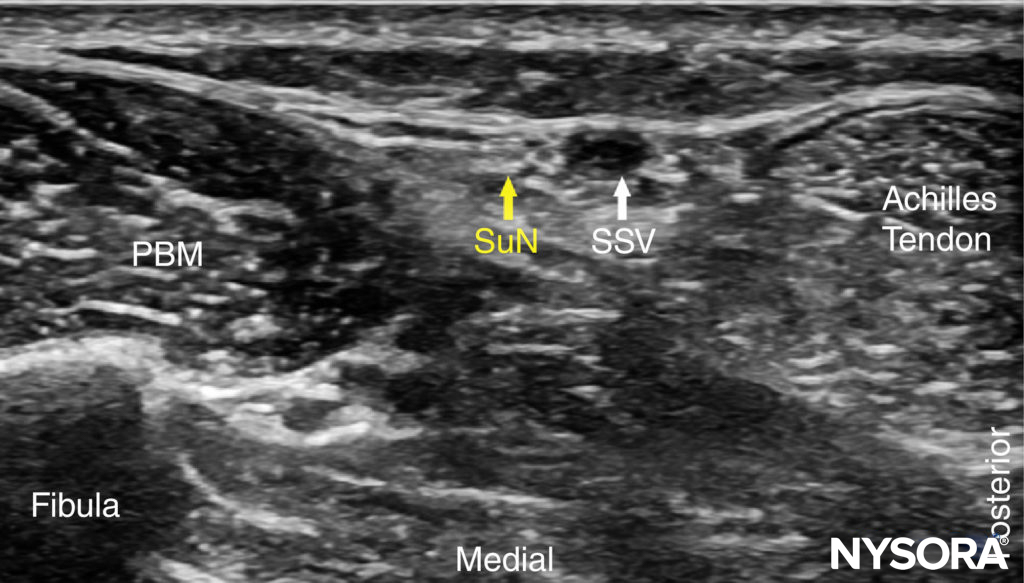

FIGURE 13. US anatomy of the sural nerve (SuN). Shown are the peroneus brevis muscle (PBM) and small saphenous vein (SSV).

The sural nerve, can be traced back along the posterior aspect of the leg, running in the midline superficial to the Achilles tendon and gastrocnemius muscles (Figures 11, 12, and 13). A calf tourniquet can be used to increase the size of the vein and facilitate its imaging; the nerve is often found in the immediate vicinity of the vein.

The sural nerve innervates the lateral margin of the foot and ankle. Proximal to the lateral malleolus, the sural nerve can be visualized as a small hyperechoic structure that is intimately associated with the small saphenous vein superficial to the deep fascia.